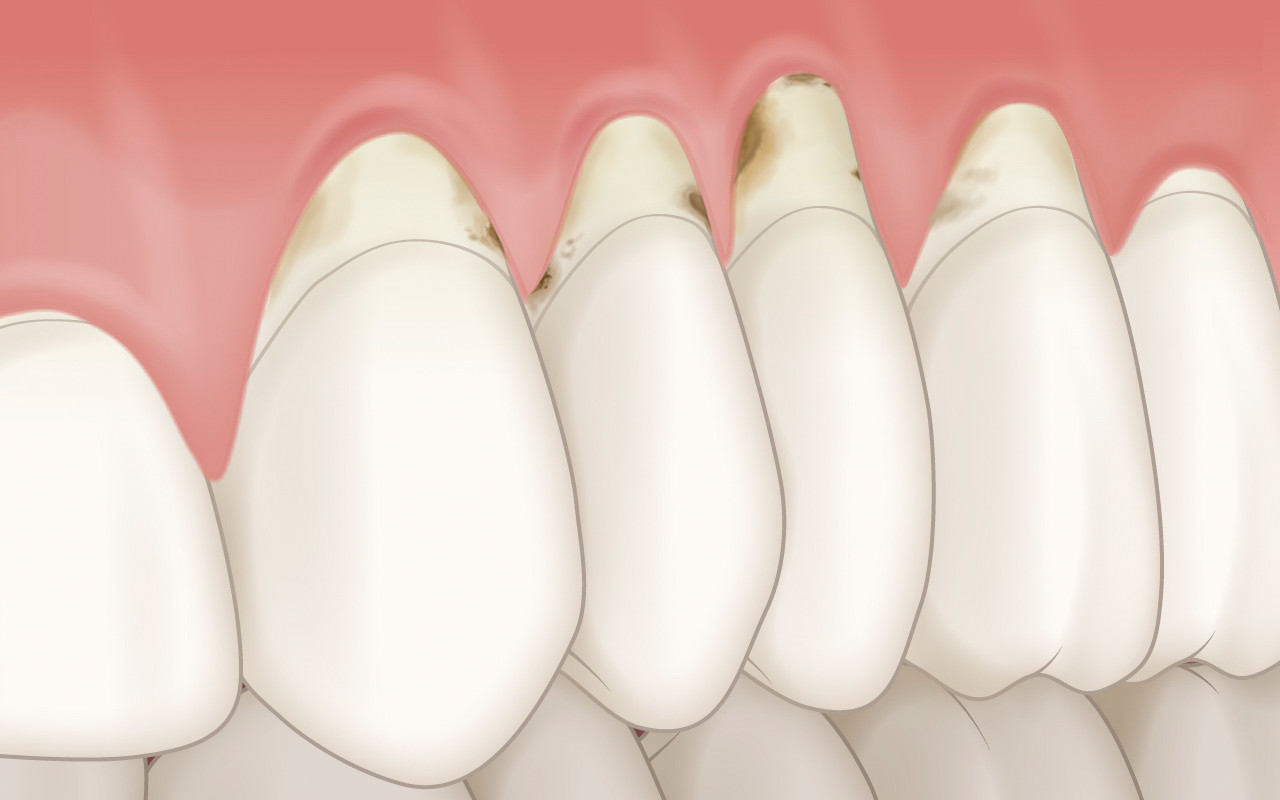

Karies

Die Hartsubstanz der entblössten Zahnwurzel ist weniger widerstandsfähig auf Karies als die Substanz der Zahnkrone (Schmelz). Die sogenannte Wurzelkaries kann dadurch rascher fortschreiten und muss deshalb besser vorgebeugt werden.

Freiliegende Wurzeloberflächen werden, wie alle anderen harten Oberflächen in der Mundhöhle auch, von bakteriellen Zahnbelägen besiedelt. Dadurch dass die Substanz der Zahnwurzel weicher ist als der darüber gelegene Schmelz der Zahnkrone, kann die Karies auf der Wurzeloberflächen früher entstehen. Diese sogenannte Wurzelkaries kann auch schneller in die Tiefe des Zahnes vordringen.

Aus diesen Gründen muss die Wurzelkaries besser vorgebeugt und die entblössten Wurzeloberflächen bei Zahnfleischrezession gut beobachtet werden. Ausserdem steigt mit dem Alter auch das Risiko, an Zahnfleischrezessionen und dadurch an Wurzelkaries zu erkranken.

Regelmässige Kontrollen in der Zahnarztpraxis ermöglichen eine gute professionelle Betreuung der betroffenen Zähne. Weiter ermöglichen die regelmässige Verwendung von fluoridhaltigen Zahnpasten eine wirksame Vorbeugung der Wurzelkaries.